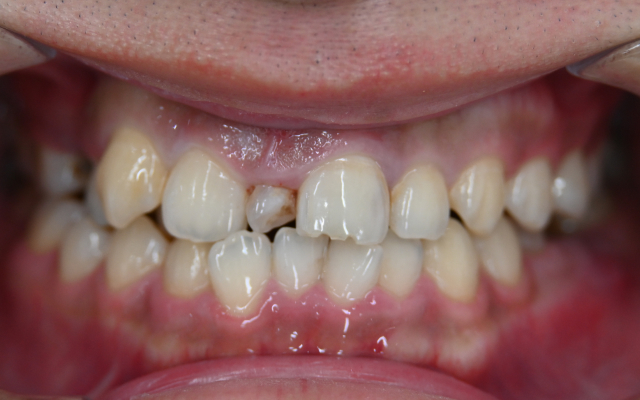

case. 02

ラミネートベニアの症例

before

after

40代 女性 削らないラミネートベニア

施術概要

セラミック治療は形の悪い差し歯や被せ物を治したり、部分的な歯並びの矯正を行うことができる治療です。短期間で歯並びの改善まで実現することが可能です。

金額

66000円(税込)×8本

期間・回数

2週間 / 2回

リスク・副作用

全ての方で、疼痛、咬合痛、冷水痛、抜歯を伴う場合は腫脹や出血などを生じる場合があります。麻酔を行う場合、腫れやむくみを感じる事があります。セラミック・仮歯が欠けたり、外れる事があります。神経の治療や抜歯が必要な場合があります。また、歯並びが変わる事により違和感を生じる可能性があります。